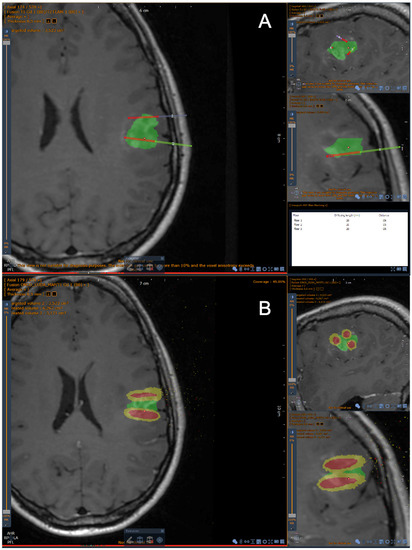

2.1.2. Segmentation Process

2.1.4. Optical Fibers Positioning